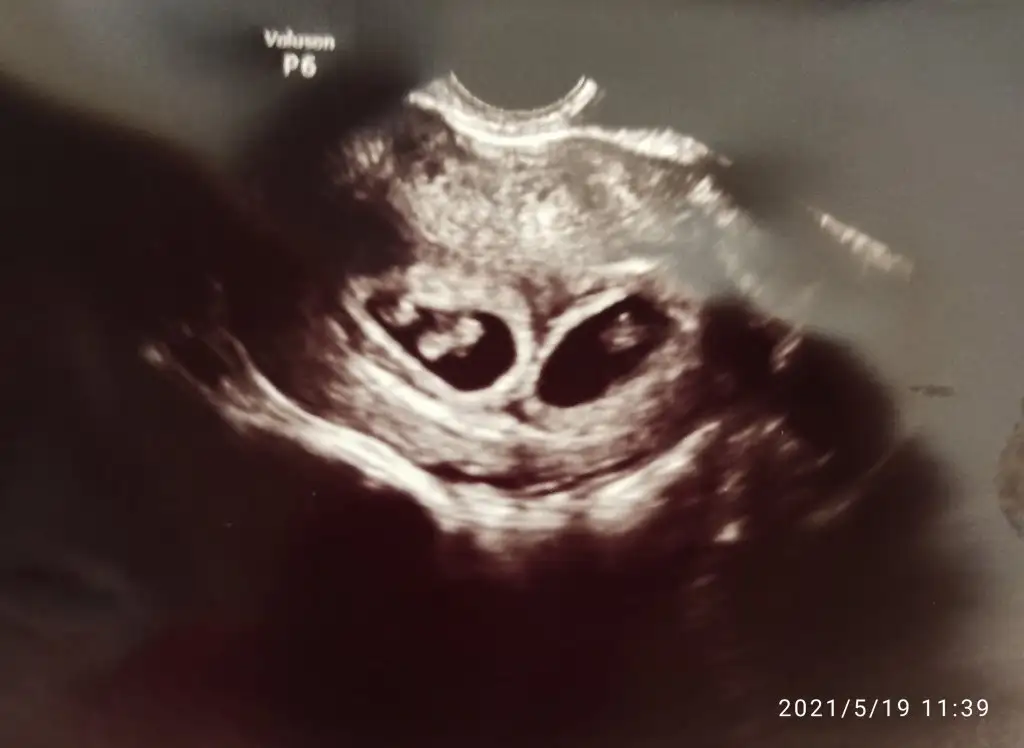

Eksik okumusum 1 yazmislar evet yaptiklari sucNisan ayında tüp bebek tedavisi oldum. Tek embriyo istememe rağmen çift embriyo transferi yapmışlar. Keseyi görmeye gittiğimde iki ayrı kese gördüm ikiz dedi. İmkansız falan dedim işte transfer günü yanlışlık olmuş falan iki embriyoyu birden transfer etmişiz dedi. Yaptığınız yasal değil dedim. Sonra bir başka doktora gittim. Aslında üçüz gebeymişim. İki kese var fakat birinin içinde iki bebek birinde tek bebek var. Kendi içinde bölünen bebek için doktoru suçlamıyorum Rabbim iki can vermiş ama ikinci embriyo için doktora ve hastaneye maddi ve manevi tazminat davası açtık bugün. Sizce mahkeme de ikinci embriyoyu biz koymadık diye inkar edebilirler mi ? Kendiliğinden oluşmuş diye. Kafam çok karıştı. Kimisi saçmalama kendi içinde bölünen gibi olsa tamam sorun yok ama ayrı ayrı iki kese var iki tane koymuş diyor. Kimisi belki kendiğinden tek koydu iki ayrı kese oldu diyor. Kafamız çok karışık. Avukatımız da hastane raporunda herşey ortaya çıkar ama burada biz haklıyız kesinlikle dedi çünkü transfer kağıdında da transfer edilen embriyo sayısı 1 yazmışlar. Ultrason görüntüsü koyuyorum anlayan varsa yarcımsı olabilir mi lütfen.Eki Görüntüle 2857134

Tek embriyodan 2 kese olmaz. Embriyo bölünürse tek kesede tek yumurta ikizi olurlar. 2 kese varsa 2 embriyo konmuş demektir.Aslında tam olarak öğrenmek istediğim şey. Tek embriyo transferi yapsa kendiliğinden iki kese olabilir mi ? Yani yaptıklarını inkar etme ihtimalleri varmı bu konuda bir bilginiz varsa yardımcı olurmusunuz daha çok.